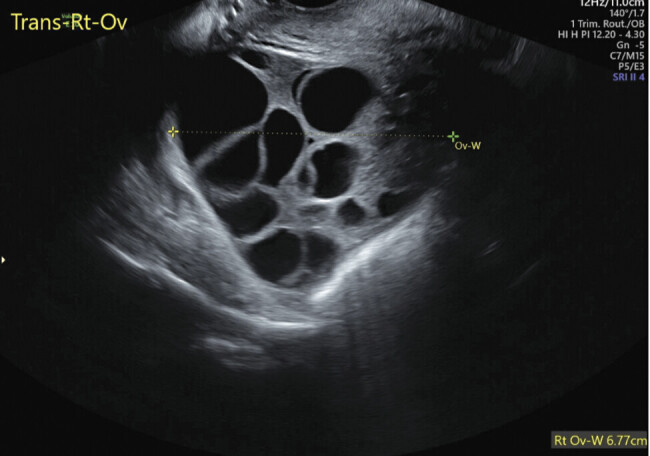

26岁女性,妊娠第1段,妊娠14周1天,出现阴道点滴和全身症状,包括心悸、呼吸短促、热不耐受、恶心和呕吐,持续2周。检查发现产妇心动过速,血压大范围升高,β人绒毛膜促性腺激素2,442,400 mIU/mL升高,促甲状腺激素抑制,T4升高,符合甲状腺风暴,可能伴有严重的先兆子痫。1经阴道超声提示部分臼齿妊娠;这后来被外科病理证实。本病例强调了葡萄胎罕见但严重的并发症,特别是部分臼齿妊娠,包括甲状腺风暴和叠加先兆子痫,强调了在三级保健中心与多学科团队管理的重要性,以优化产妇结局。2 3。

A 26-year-old woman, gravida 1 para 0 at 14 weeks' 1-day gestation, presented with vaginal spotting and systemic symptoms, including palpitations, shortness of breath, heat intolerance, nausea, and vomiting for 2 weeks. Workup revealed maternal tachycardia, severe-range blood pressure, elevated beta human chorionic gonadotropin of 2,442,400 mIU/mL, suppressed thyroid stimulating hormone, and elevated T4, consistent with thyroid storm with possible preeclampsia with severe features. 1 A transvaginal ultrasound suggested a partial molar pregnancy; this was later confirmed by surgical pathology. This case highlights the rare yet serious complications of hydatidiform mole, in particular, a partial molar pregnancy, including thyroid storm and superimposed preeclampsia, emphasizing the importance of management at a tertiary care center with a multidisciplinary team to optimize maternal outcomes. 2 3.